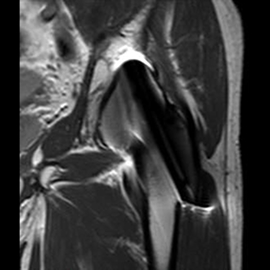

MRIの検査画像例

MRI

PHILIPS社製Ingenia 1.5TMRIを使用しています。開口径が従来の装置より広いワイドボアタイプとなり、より圧迫感の少ない、患者さんに優しい検査環境を実現できます。また、世界初のデジタルコイルを採用しており、ノイズが少なく診断能の高い画像が得られるようになりました。

新しい技術として、体動補正技術(MultiVane)や金属アーチファクト抑制技術(MARS)が使えるようになり、画質が格段に改善しております。